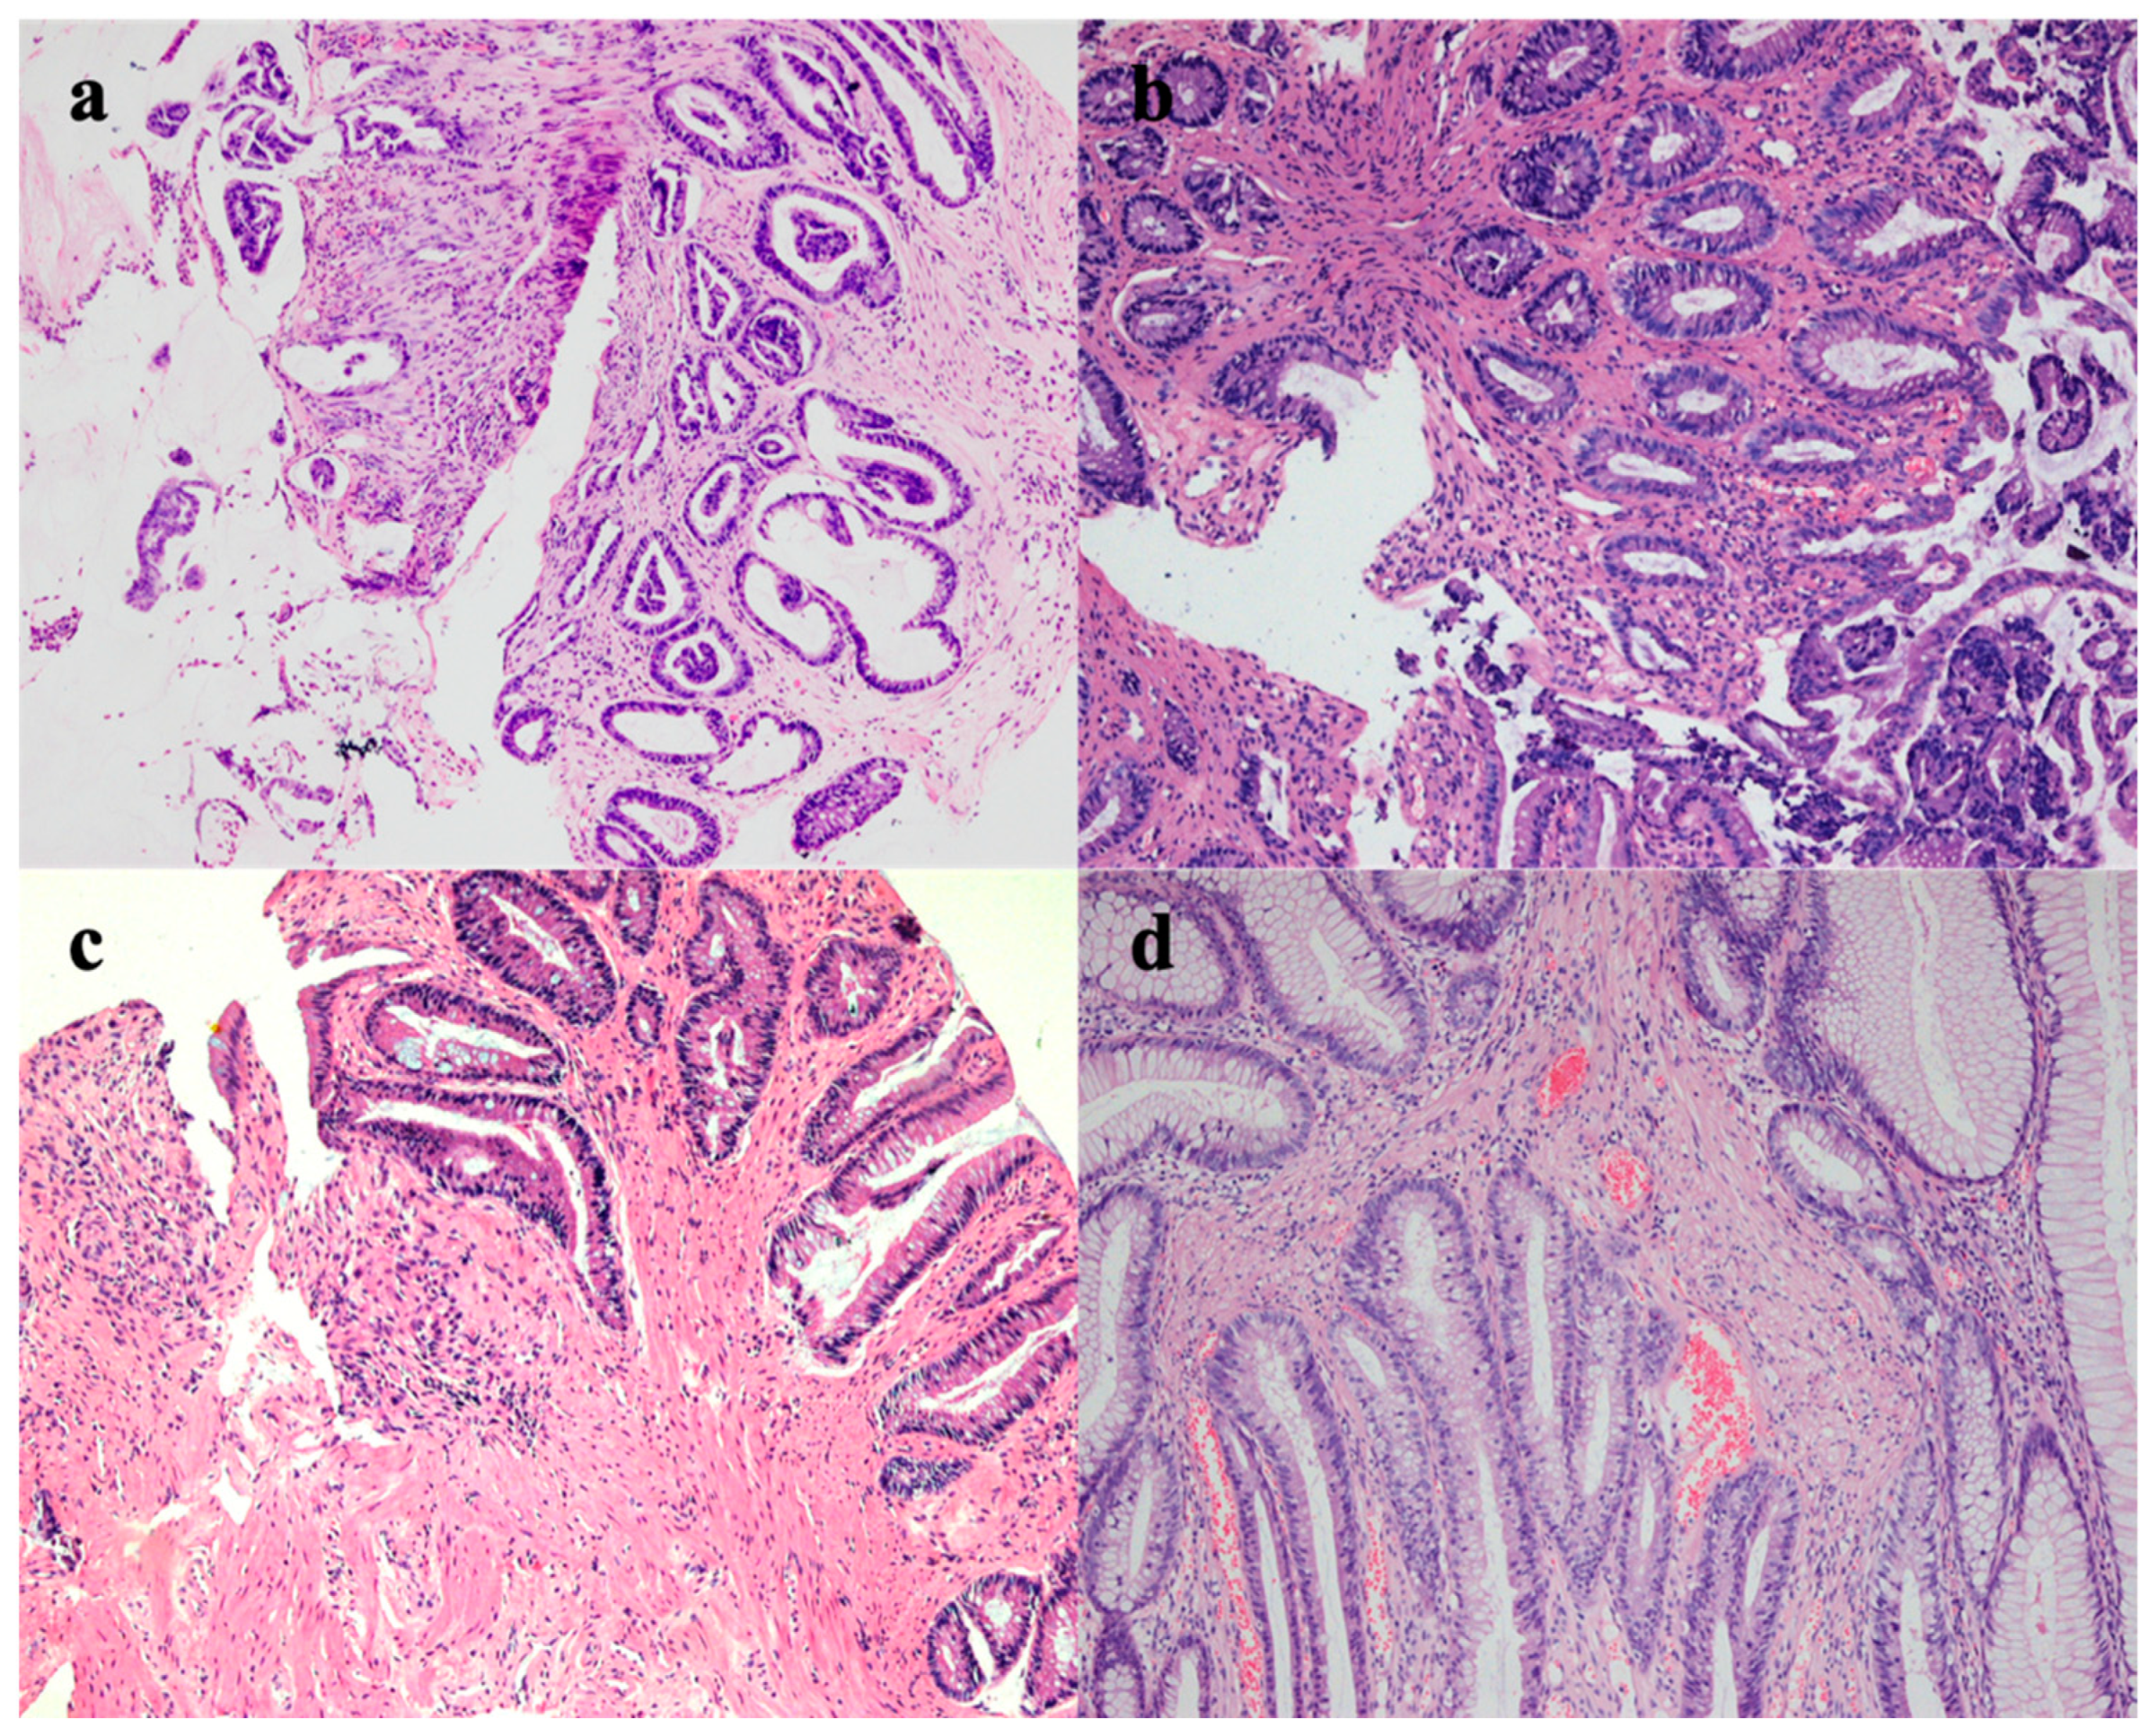

2. Case Report